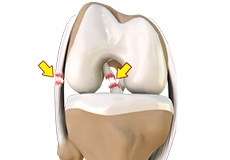

Meniscal Tear

A meniscal tear is a common knee injury in athletes, especially those involved in contact sports. A sudden bend or twist in your knee causes the meniscus to tear. Elderly people are more prone to degenerative meniscal tears as the cartilage wears out and weakens with age.